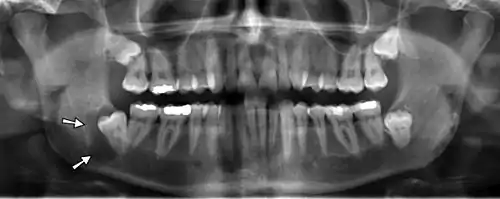

X-ray64A

Arrows point to two vertical white lines which is how calcifications in the first part (proximal component) of the internal carotid artery appear on panoramic radiographs.

Panoramic radiographs have the capability to demonstrate a portion of the neck and display atheromas (calcifications in the carotid artery) which are an indication of both local and generalized (systemic) atherosclerosis. Atherosclerosis of the coronary arteries leading to myocardial infarction (heart attack), and atherosclerosis of the carotid artery leading to stroke are the number one and number three most common causes of death in the United States.[6]